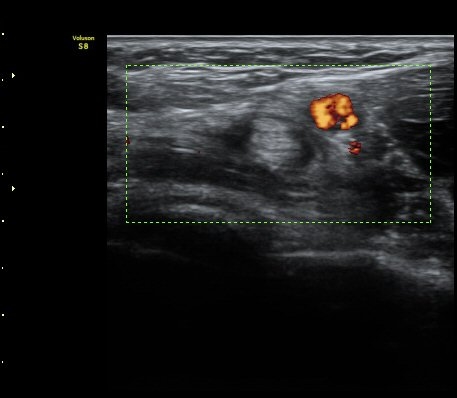

ÆÈ²ÞÄ¡ ¾Õ Ⱦ´Ü¸é°Ë»ç¿¡¼­ À̵ιڱÙÀÌ ÈûÁÙ·Î ÀÌÇàµÇ´Â °ÍÀÌ °üÂûµÈ´Ù(±×¸² 1, 2).

ŽÃËÀÚ¸¦ Á¶±Ý ¸»´ÜÀ¸·Î À̵¿ÇÏ´Ï À̵ιڱ٠ÈûÁÙÀÌ ¶Ñ·ÈÇÏ°Ô °üÂûµÇ°í ÇÔÁÙ ÁÖÀ§¿¡

¼ö¾×Àú·ù°¡  º¸ÀδÙ(±×¸² 3, 4, 5, 6)